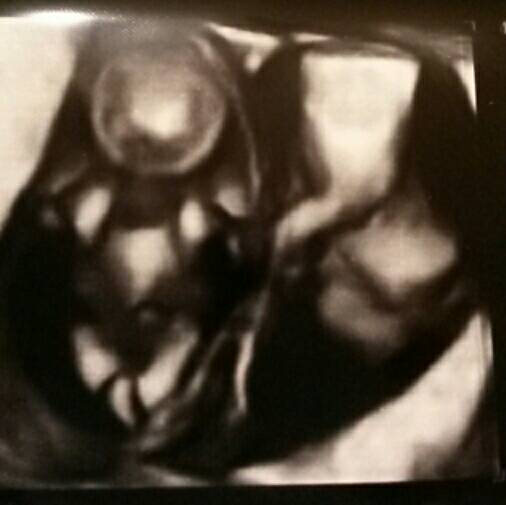

Kävimme tänään np-ultrassa. Kaksi kaverusta siellä edelleen jumppasi. Niskaturvotusta oli kummallakin alle 1mm ja muutenkin sikiöillä oli kaikki palikat paikoillaan. Kahden kätilön voimin selvittivät sitten, minkä tyyppinen raskaus on kyseessä ja molemmille löytyivät omat istukat ja kaikki muukin oli omaa. Eli paras mahdollinen tilanne tässä vaiheessa. Kokoa kaveruksilla oli sen verran, että vastaavat viikkoja 12+1 ja 11+6. Ihan viikkoja vastaavat ovat siis.

Saatiin mukaan ihan hirveästi kuvia ja ultrassakin meni aikaa toista tuntia. Olisi ruutua kyllä pidempäänkin vielä katsellut. Sen verran veikeän näköistä oli kaverien meno. Selvästi olivat jakaneet vuorot, että kun toinen lepää, toinen riehuu ja sitten vaihdetaan. Onneksi asennot olivat hyvät, että kätilö sai kaikki tarpeelliset mitat otettua.